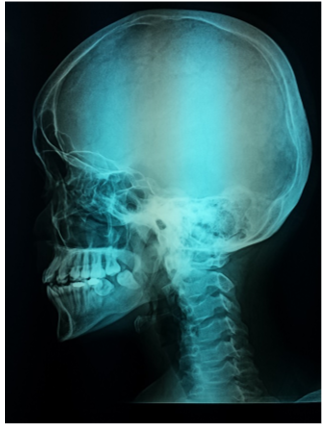

Figure 6 Lateral skull X-ray shows effacement (floating) of the teeth due to loss of alveolar lamina dura..